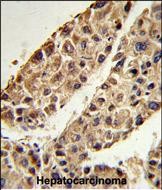

IHC 1/100-1/500 Human,Mouse,Rat

Antibodies targeting ITIH2 are primarily used in research to study its biological functions and pathological associations. ITIH2 has been implicated in inflammatory diseases, cancer progression, and liver fibrosis, with altered expression levels observed in conditions like hepatocellular carcinoma and chronic hepatitis. Its role in modulating hyaluronan-rich matrices also links it to tumor microenvironment regulation.

ITIH2-specific antibodies enable detection and quantification of the protein in biological samples (e.g., serum, tissue sections) using techniques like ELISA, Western blot, and immunohistochemistry. Recent studies explore ITIH2 as a potential biomarker for disease progression or therapeutic response. However, its complex formation with other ITIH members and post-translational modifications pose challenges for antibody specificity, requiring careful validation in experimental settings. Ongoing research continues to clarify ITIH2's dual roles in physiological maintenance and disease mechanisms.